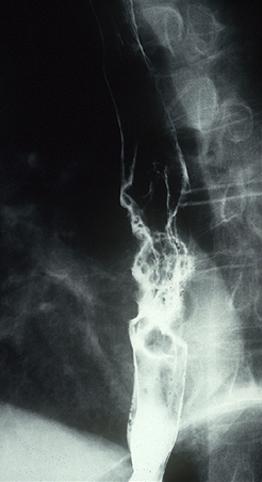

Criteria of Hist.ClassificationMalignant epithelial tumor/Squamous cell carcinoma

LocationEsophagus/More than one of the above

Technique, MethodX-ray

Macroscopic TypesType 2 Ulcerated type with clear margin/

Size40 -

Depth of Tumor Invasionserosa (adventitia)